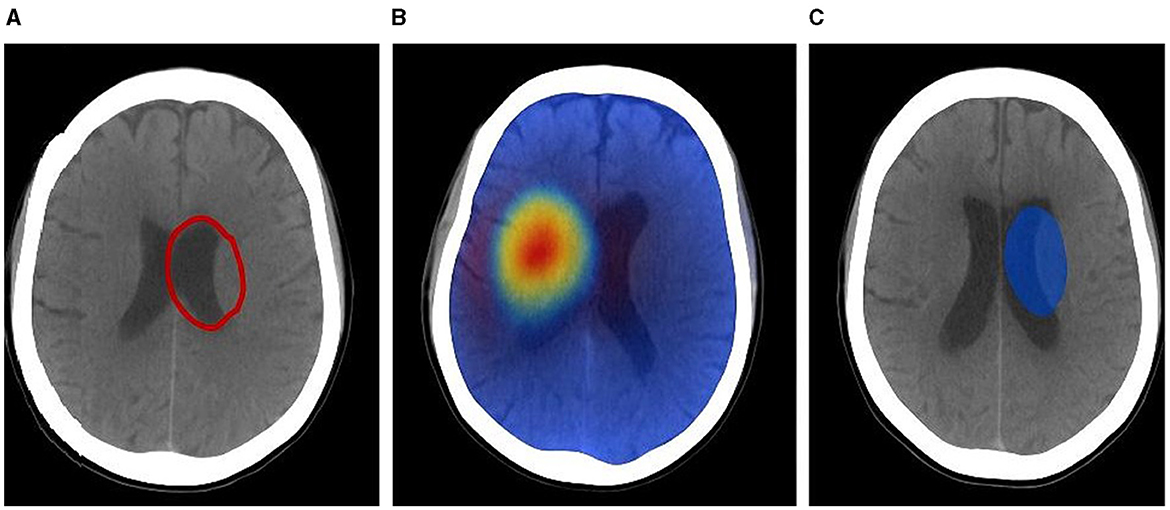

4.4.1 Tumor margin refinement with CE maps

Figure 7 illustrates a typical case where standard Grad-CAM saliency maps highlight a broad region around the lesion, while CausalX-Net CE maps sharply delineate the enhancing tumor boundary. Across all 30 cases, CE maps improved boundary agreement with ground truth contours (Dice of manual vs. assisted contours: 0.86 vs. 0.79, p < 0.001) and reduced inter-rater variability (Hausdorff 95th percentile: 2.9 mm vs. 4.1 mm). Radiologists reported that CE maps particularly helped separate enhancing tumor from surrounding edema in heterogeneous lesions.

Figure 7

Tumor margin refinement: (A) ground truth, (B) Grad-CAM saliency, (C) CausalX-Net CE map overlaid on T1CE. CE maps confine to true ET boundaries, reducing over-segmentation.